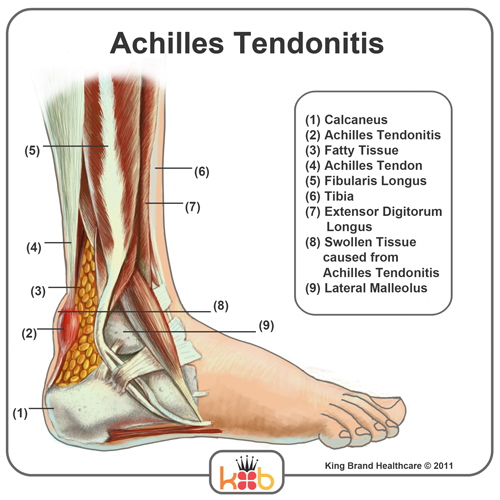

King Brand Ankle Images